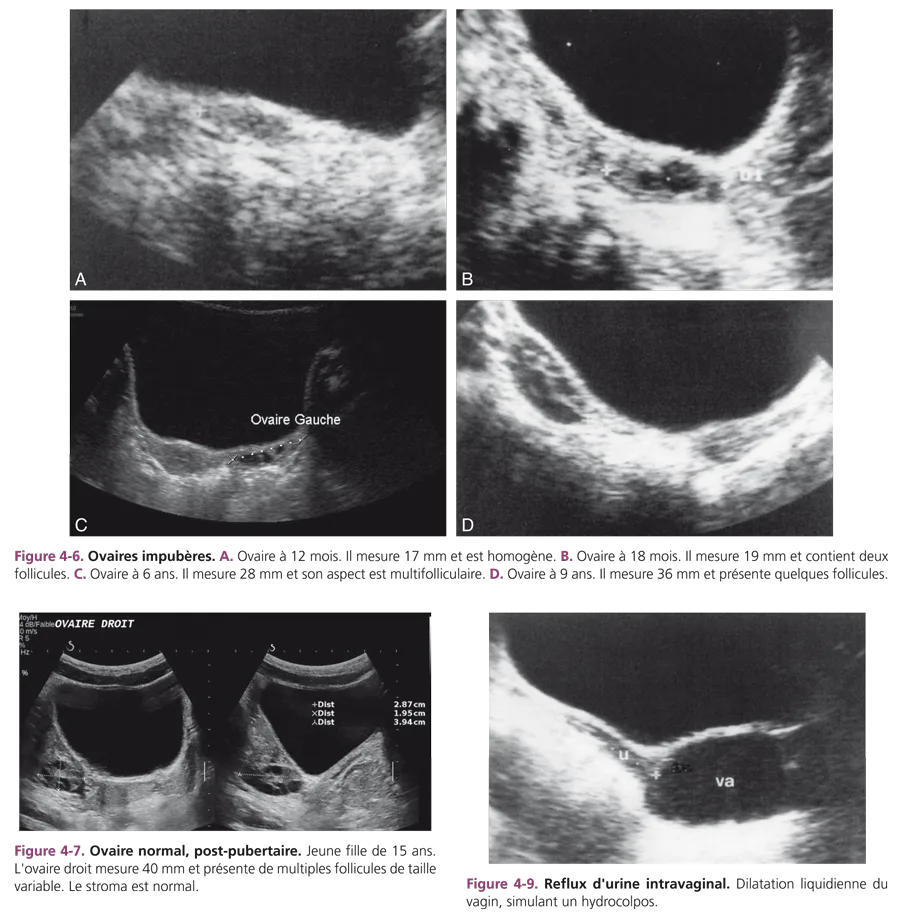

Pendant l’enfance, la taille de l’ovaire croît régulièrement. Chez la fillette avant 4 ans, le volume ovarien est en général inférieur ou égal à 1 cm3, soit en mensurations moyennes : 2 cm de longueur × 1 cm de largeur et 1 cm d’épaisseur. Entre 6 et 8 ans, la longueur ovarienne excède souvent 2,5 cm. À partir de 9 ans, l’ovaire mesure 3 cm ou plus. Le développement ovarien précède celui de l’utérus et apparaît antérieur à l’apparition des premiers signes cliniques du développement pubertaire (fig. 4-6). Chez l’enfant impubère, l’ovaire se présente comme une structure ovoïde, hypoéchogène, parfois homogène, mais le plus souvent hétérogène, en rapport avec l’existence de microfollicules dont la taille reste inférieure à 5 mm. Cet aspect microfolliculaire se retrouve chez 93 % des filles entre 2 et 11 ans. À tout âge, il est normal d’observer des follicules ovariens et leur nombre augmente avec l’âge. La constatation d’ovaires plurifolliculaires en période prépubertaire est banale [3–5]. À la puberté, les ovaires sont considérés comme stimulés, développés, lorsque leur longueur est supérieure à 3 cm ou leur volume supérieur à 3 cm3 et qu’ils présentent une activité folliculaire avec visibilité de plusieurs follicules. Cet aspect, associé à un développement utérin, marque la puberté en cours. Après la puberté, pendant les premières années de menstruations, il est habituel de constater un aspect d’ovaires multifolliculaires, avec présence de nombreux follicules de taille variable, occupant le volume ovarien. Cet aspect, très probablement lié aux cycles initiaux anovulatoires (fig. 4-7), est tout à fait normal.

Enfin, l’existence d’un reflux d’urine dans le vagin est banale. Il peut simuler un hydrocolpos mais disparaît après miction ou en position debout (fig. 4-9). Les principales indications de l’échographie pelvienne chez l’enfant sont mentionnées dans l’encadré 4-1.